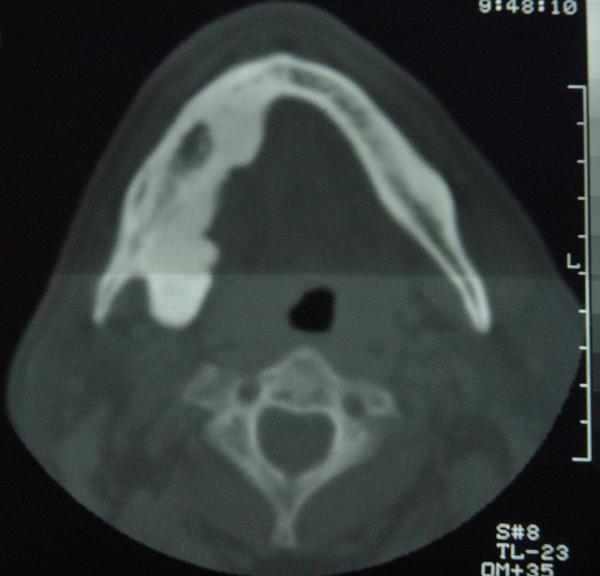

标题: CT12465:下颌骨肿瘤,请会诊 [打印本页]

标题: CT12465:下颌骨肿瘤,请会诊

发现下颌骨肿瘤近30年.逐渐增大.

考虑右侧下颌骨水平部及升部骨纤维异常增殖症可能性大。

考虑右侧下颌骨骨化性纤维瘤。